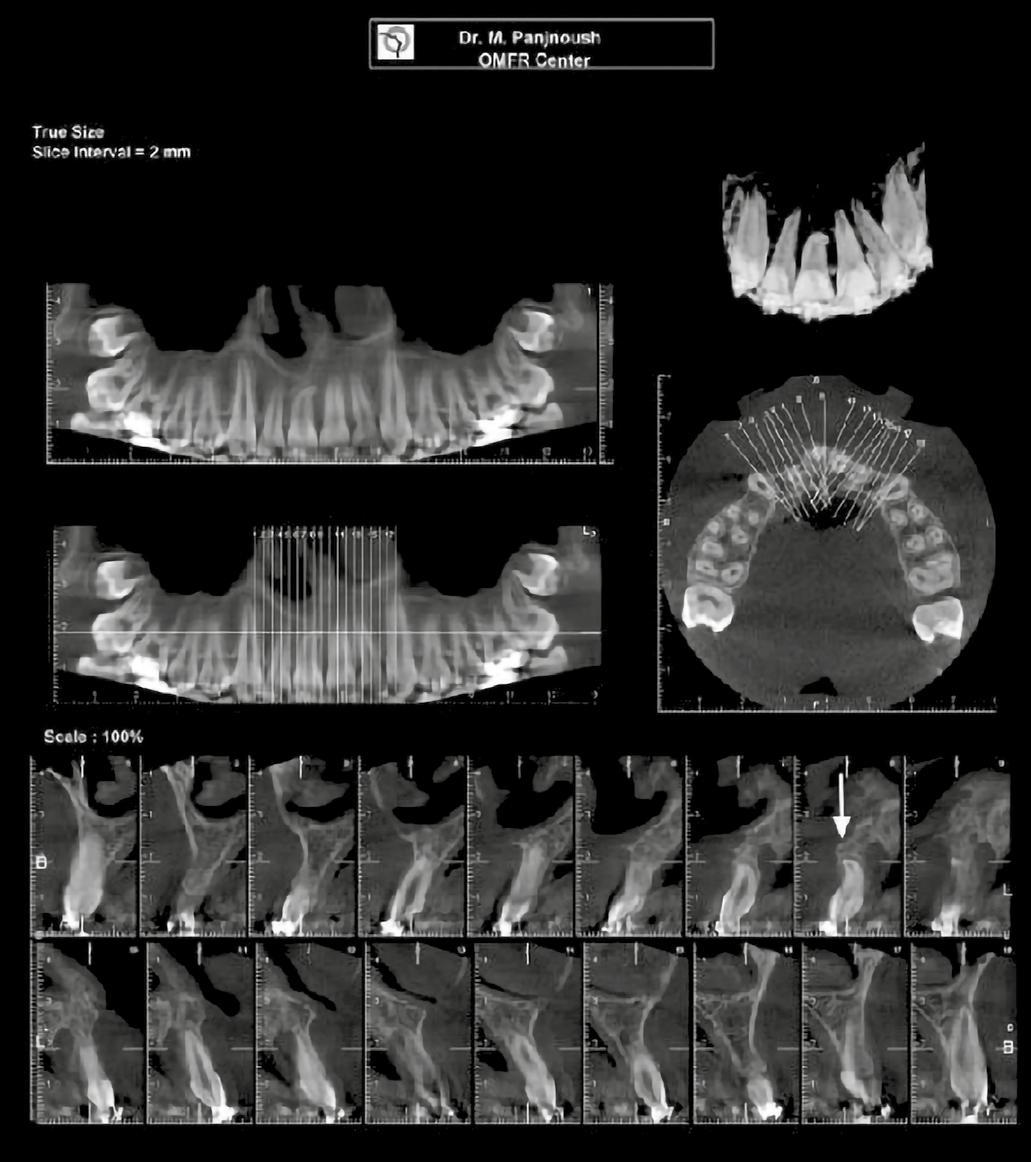

A 10 éves férfi páciens a felső frontfogai késői/nem megvalósuló előtörése miatt kereste fel a rendelőnket. A klinikai és a radiológiai vizsgálat során a jobb felső nagymetszőfog impakcióját észleltük (1. ábra). A fog horizontális tengelyállással és dilacerált gyökérrel rendelkezett. A felső dentális középvonal a fogak vándorlása miatt jelentős mértékben elcsúszott. A bal felső kismetszőfog is rendkívül kedvezőtlen pozícióba került.

Dr. Kazem Dalaie, dr. Samin Ghaffari, dr. Mazir Mir (Irán, Németország) 1. a ábra: Az intraorális felvételen jól látható a jobb felső nagymetszőfog lehetséges impakciójára utaló foghiány.

1. b ábra: A panoráma röntgenfelvételen megfigyelhető a teljes impakcióban lévő jobb felső nagymetszőfog. 1. c ábra: A CBCT felvétel is igazolja a jobb felső nagymetszőfog impakcióját.